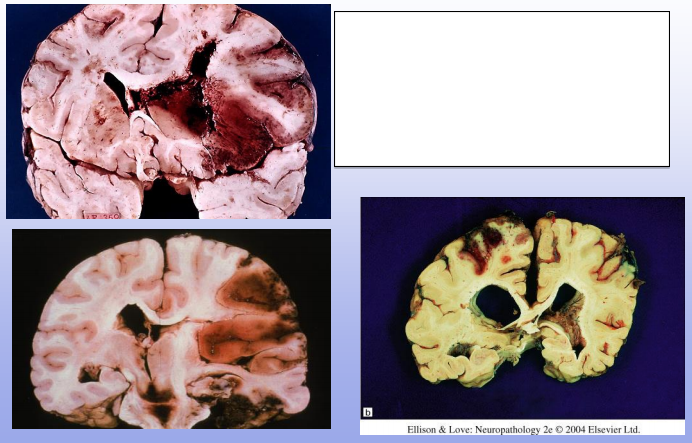

Hemorrhagic Infacts; can be venous (thrombus) or arterial (ischemia and reperfusion)

Venous Infarcts; most commonly seen parasagittally (in superior sagittal sinus distribution) or distribution of transverse sinus

Top: bilateral PCA infarcts from emboli can often become hemorrhagic (and can be multifocal)

Bottom: small clot/embolus (arrow) with surrounding hemorrhagic infarct

Hypertensive hemorrhage; tend to occur more centrally in brain (basal ganglia, thalamus)

Top R: Charcot-Bouchard aneurysm of lenticulostriate vessels of BG, associated wit HTN

Bottom R: thickened BV wall, loss of SM